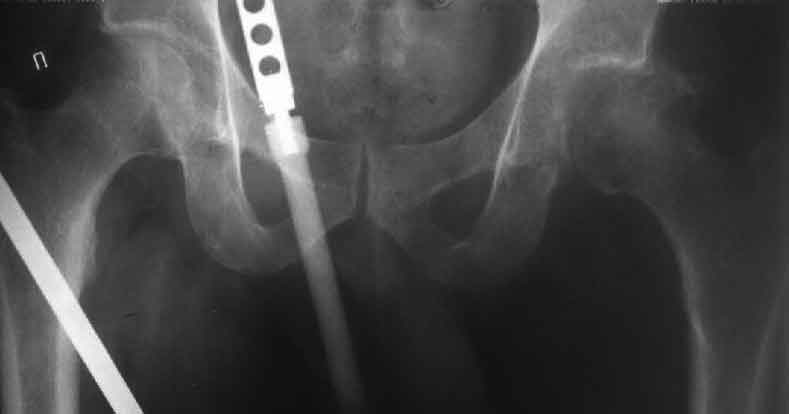

А за счет чего такое укорочение? По снимку не видно соответствующего дефекта. Ну плюс приводящая контрактура - но все равно как-то уж больно много. Может, сделать снимки и таза обзорный с обоими проксимальными отделами бедра, и коенный суставов с приложенной линейкой какой?

Судя по снимку, максимум истинное укорочение около 4 см, что может быть коррегировано интраоперационно. Вопрос в другом: куда ставить ацетабулярный компонент в истинную или во вновь сформированную ( впадина диспластичная).

Невозможно не согласиться с Анатолием, чтобы заниматься адекватным планированием как минимум прямая проекция таза должна быть сделана, как

The X ray that you provided does not show 8 cm of shortening. Perhaps you could send one showing the whole pelvis and proximal femurs.

I agree with Dr Eid's comments. The origin of the 8 cm leg length difference is a puzzle. Is this a clinical measurement? In that case contracture of the joint might affect the measurement. Can we see an AP pelvis to include both hip joints (including a calibration object with a known length) so that the difference in leg lengths that can be ascribed to the hip deformity and bony reabsorption can be measured. This sort of xray will help with templating for the TJR also. I would be very tempted to do a one stage procedure and accept some shortening. Shoe lifts should take care of a 3-4 cm difference.

До травмы проблем с ногой не было. Укорочения, болей и т.п. не отмечал. Сегодня перемерял укорочение - меньше 7 см намерять не

получается :)

По уровню малых вертелов (с учетом рентгеновского увеличения) получается 5 см. Клинически ногу низвести путем тракции невозможно. Из движений - сгибание до 40*, остальные движения "символические".